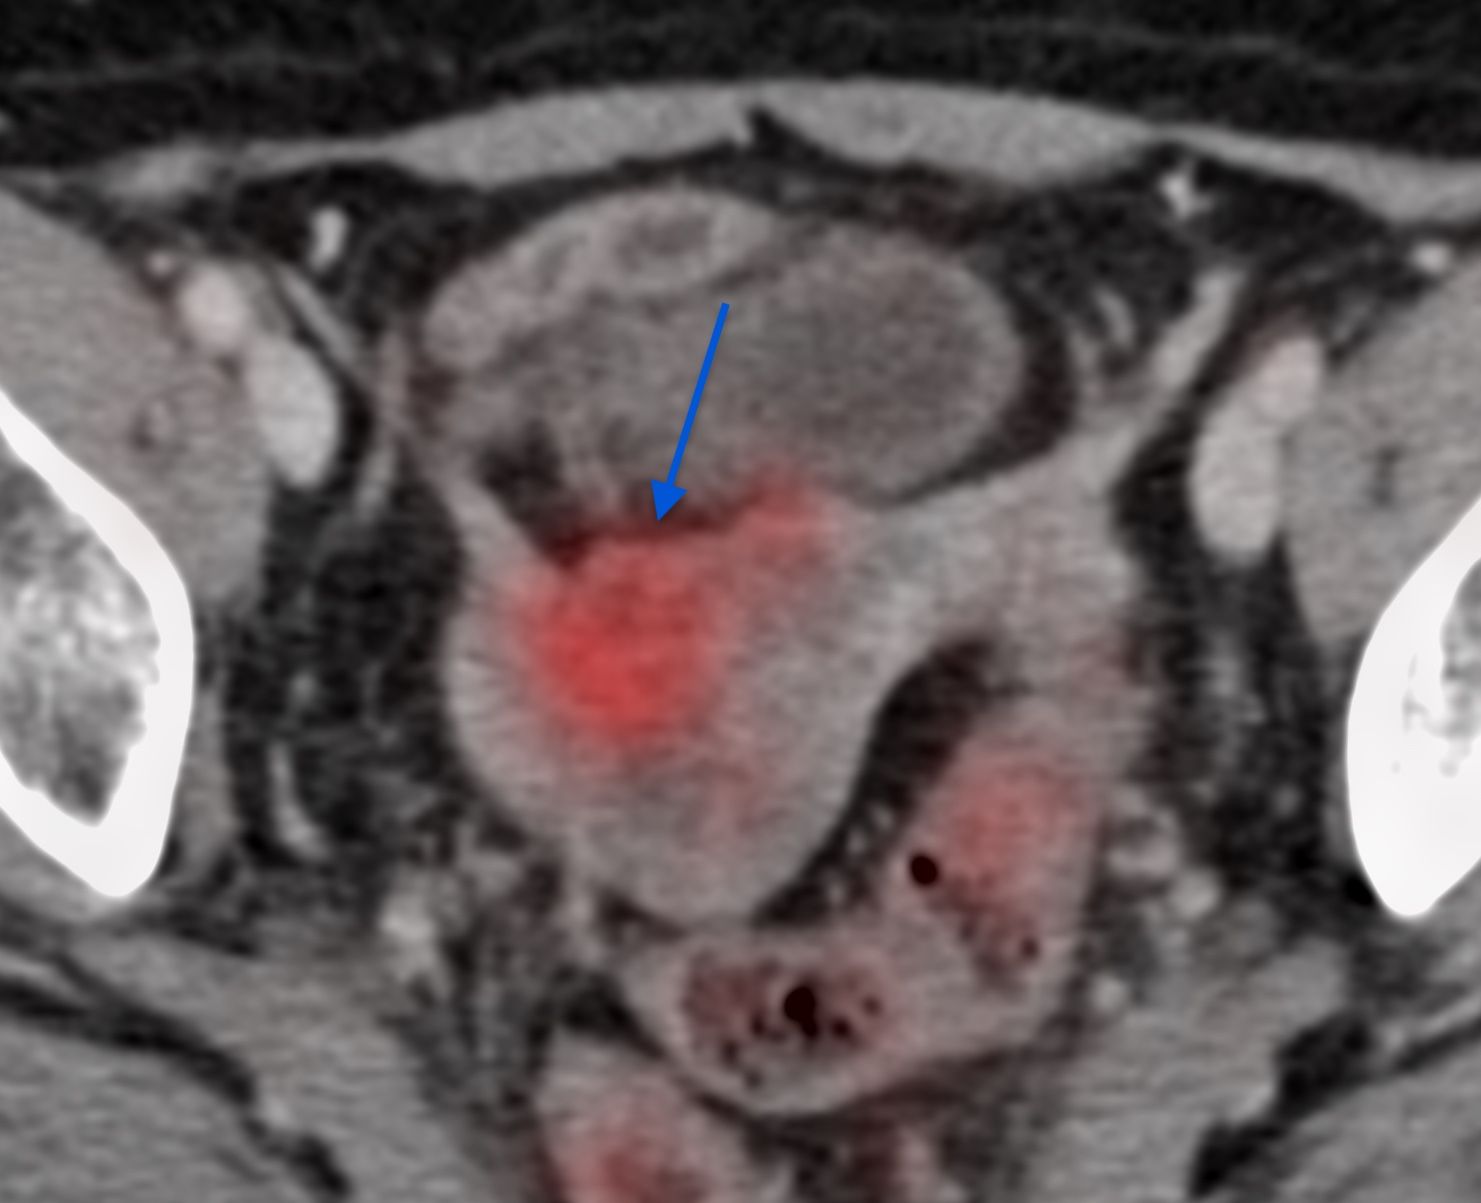

This 68-years old had carcinoma cervix for which she treated. There was recurrence in the uterine cavity, but the lesion could not be targeted easily for a biopsy due to a high-grade lower uterine stenosis and both, USG guided transvaginal and hysteroscopy guided biopsy were deemed not possible and the patient was referred for a CT guided biopsy.

The video below discusses the case, the approach and the way the biopsy was done followed.